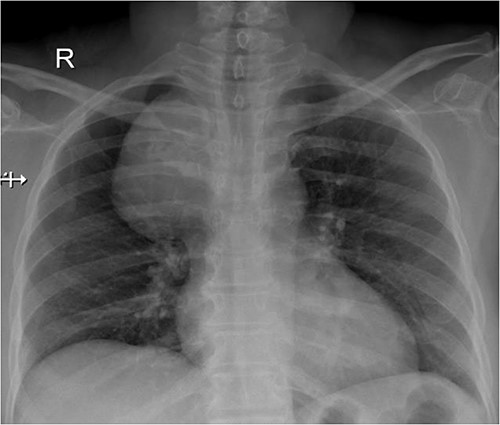

A 57-year-old female came with chest discomfort and cough since 1 month. The chest X-ray (Fig. 1) showed mass in the superior mediastinum. CECT thorax (Fig. 2) revealed the soft tissue density 7 cm × 7 cm (Fig. 3) in superior mediastinum abutting subclavian artery, azygous vein, anteriorly displacing superior venacava, anteromedially abutting arch of aorta, posteromedially compressing trachea and abutting right main bronchus. A 4.9 cm × 5 cm mass in the left side superior mediatinum was seen abutting internal jugular vein and brachiocephalic artery. USG showed the presence of normal thyroid in the neck. CT guided biopsy from the right mass showed ectopic thyroid tissue (ETT)-colloid goiter. Due to close proximity with major vessels sternotomy done. Mass in the left side 5 cm × 5 cm (Fig. 4) in the superior mediastinum was identified, on dissecting superiorly, which was free from the thyroid in the neck and abutting the IJV, brachiocephalic artery and left innominate vein that were separated with meticulous dissection.

The right mass (Fig. 5) was even bigger and needed an extension of incision into the neck (Fig. 6). About 7 cm × 7 cm noted to be displacing Superior venacava anteriorly that was dissected from it, separated from the first rib and subclavian artery meticulously taking care not to damage any major structure. Both masses were excised. These masses were not connected in any way with each other as well as with the orthotopic thyroid in the neck. Post-op was uneventful. Thyroid functions were normal. Thyroid scan (Fig. 8) showed no evidence of a thyroid tissue in the mediastinum and no other ectopic thyroid was present other than the orthotopic thyroid tissue in neck. The patient was discharged on POD 10 without any symptoms. The histopathological tissue diagnosis showed a colloid goiter (Fig. 7). All data kept in our database.